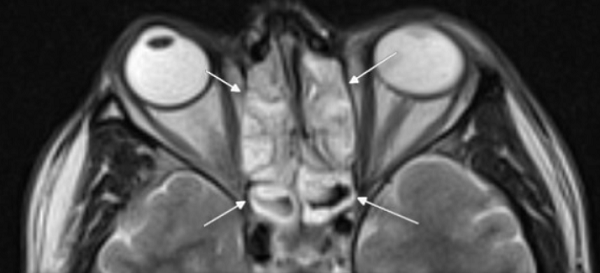

Концентрическая воспалительная гипертрофия ячеек решетчатой кости (указана стрелками)

- Сканирование (активный этап МРТ носовых пазух). Рентгенолог дает указание соблюдать неподвижность и включает томограф. Во время проведения процедуры лучше полностью расслабиться и успокоиться. Для профилактики искажения снимков нельзя двигаться, нежелательно открывать глаза. Сканирование длится 15 минут. При проведении МРТ с контрастным усилением процедуру прерывают для подачи усилителя. После внутривенной инъекции препарата работу томографа возобновляют. Применение контрастного вещества продлевает время исследования носовых пазух на 15 минут.